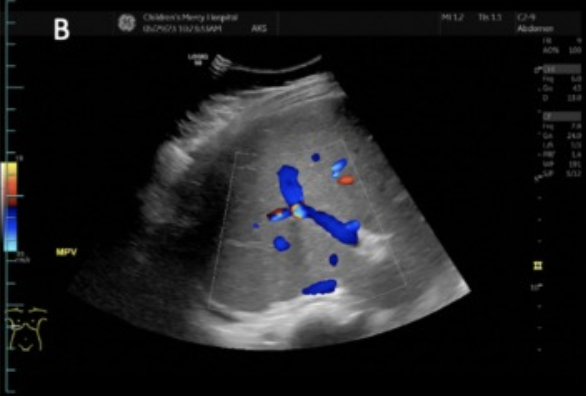

2D US: early stages → hepatomegaly, later/progressive → right ± left lobe atrophy, compensatory caudate lobe hypertrophy, fibrotic heterogenous liver changes, nodular contour, ± hepatic vein compression w/ flattened waveform, PHTN → ascites, splenomegaly, MPV dilation ± reversal of flow

color doppler: no communication between hepatic vein and IVC